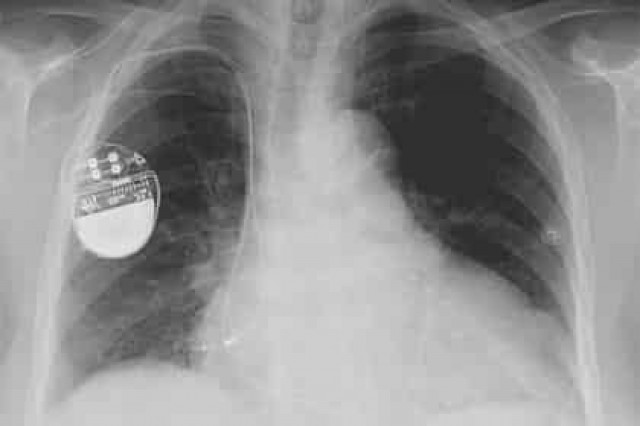

Исследователи информационной безопасности нашли способ взломать прошивку кардиостимуляторов фирмы Medtronic. Они позволяют злоумышленникам дистанционно управлять имплантами, подвергая опасности жизни владельцев.

Уязвимость состоит в том, что прошивка не защищена цифровой подписью. При этом обновления для программистов медицинских аппаратов передаются по незащищенным каналам. Это позволяет внедрять вредоносную прошивку, способную управлять количеством ударов сердца пациента через стимулятор.